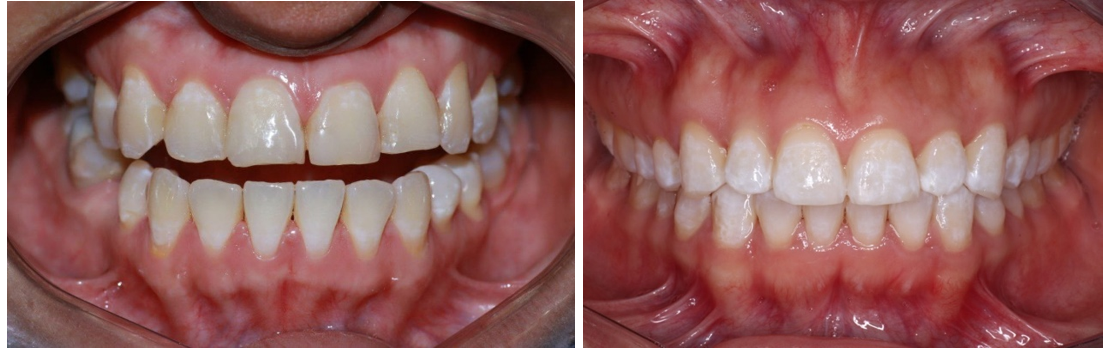

El estudio involucró la participación de dos pacientes adultos jóvenes, sin patología sistémica aparente, con sospecha de diagnóstico de fluorosis dental, a los cuales tras examen clínico se determinó la presencia de fluorosis dental en las superficies vestibulares de los dientes permanentes superiores anteriores (figura 1), en un grado leve según el Índice de Dean basado en lo expuesto por Azpeitia-Valadez,(19) los pacientes fueron invitados a participar del estudio, explicando minuciosamente las implicaciones del estudio, tras lo cual mediante firma de consentimiento informado aceptaron formar parte del estudio.

Figura 1. Diagnóstico inicial del paciente mediante Escala de Dean: fluorosis dental grado leve